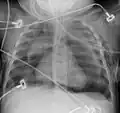

-

Neumomediastino y neumotórax derecho tras fractura de la primera costilla en accidente de bicicleta de montaña. -